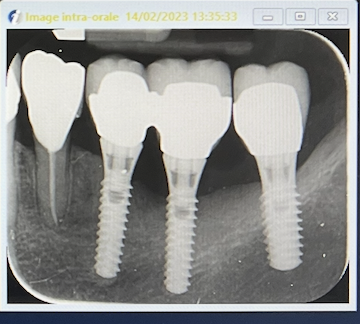

radio le 14/02/2023